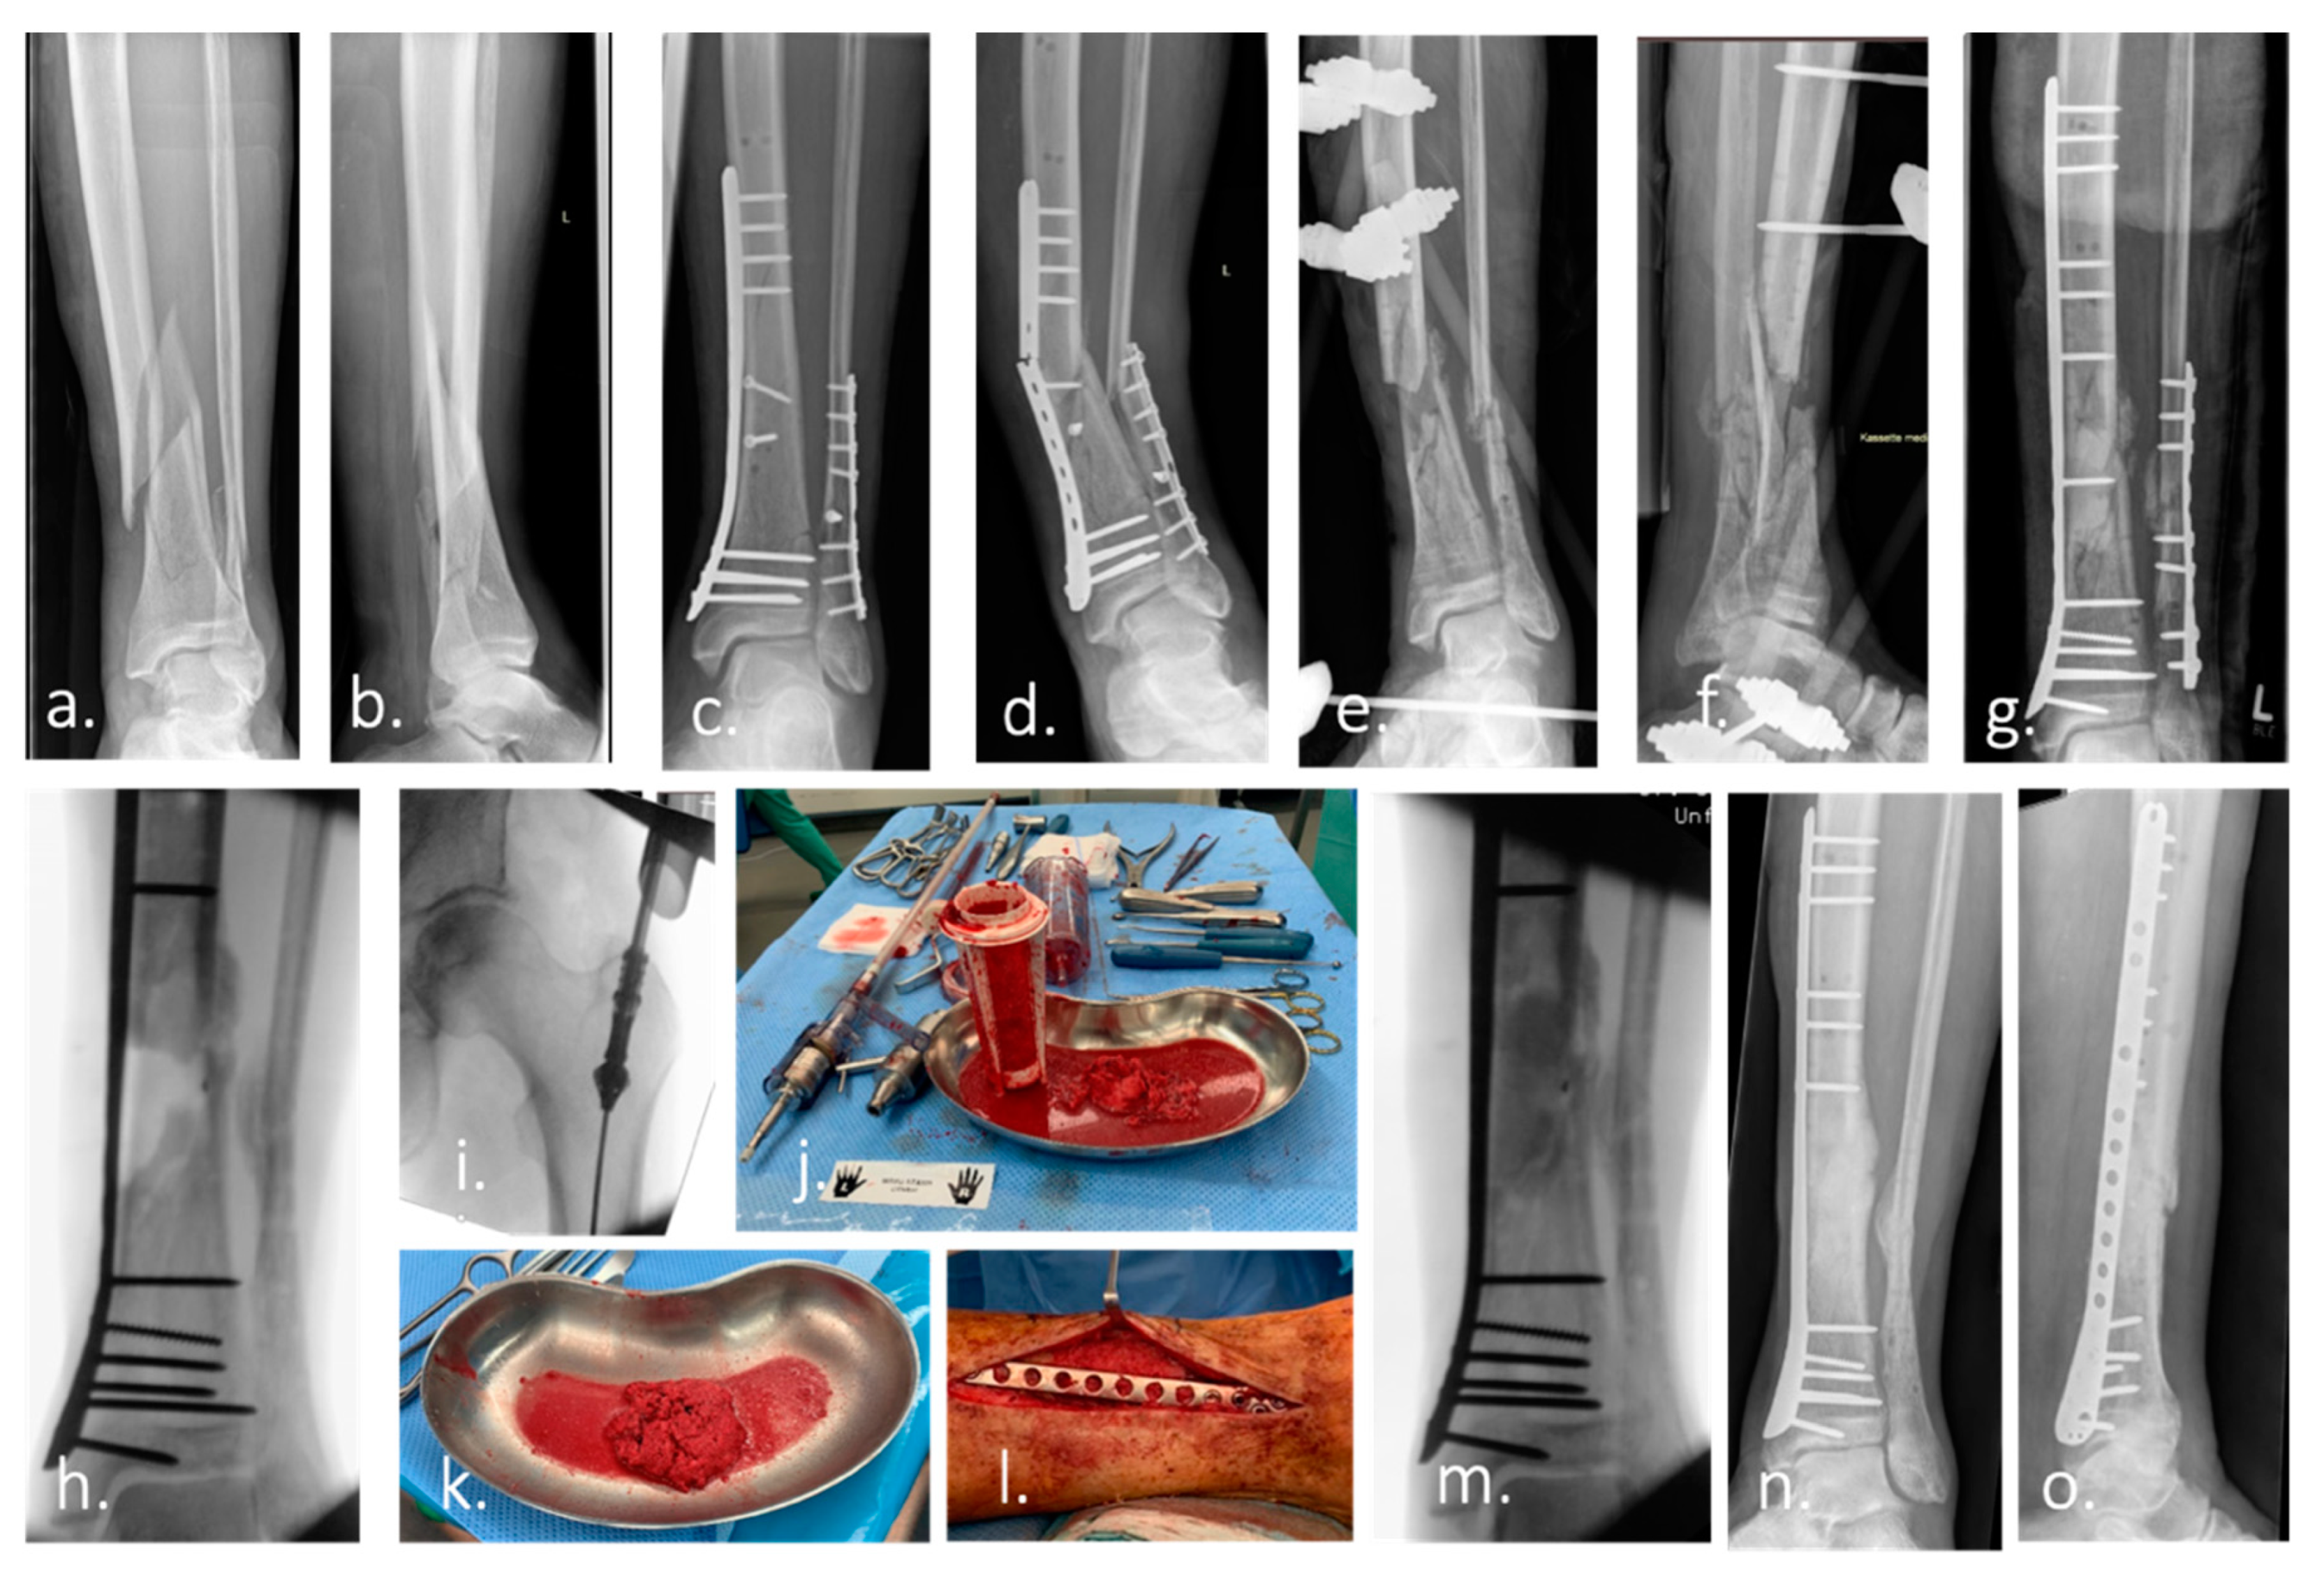

- Masquelet, A.C.; Fitoussi, F.; Begue, T.; Muller, G.P. Reconstruction of the long bones by the induced membrane and spongy autograft. In Annales de Chirurgie Plastique et Esthetique; Elsevier: Paris, France, 2000; Volume 45, pp. 346–353. [Google Scholar]

- Morelli, I.; Drago, L.; George, D.A.; Gallazzi, E.; Scarponi, S.; Romanò, C.L. Masquelet technique: Myth or reality? A systematic review and meta-analysis. Injury 2016, 47, S68–S76. [Google Scholar] [CrossRef]